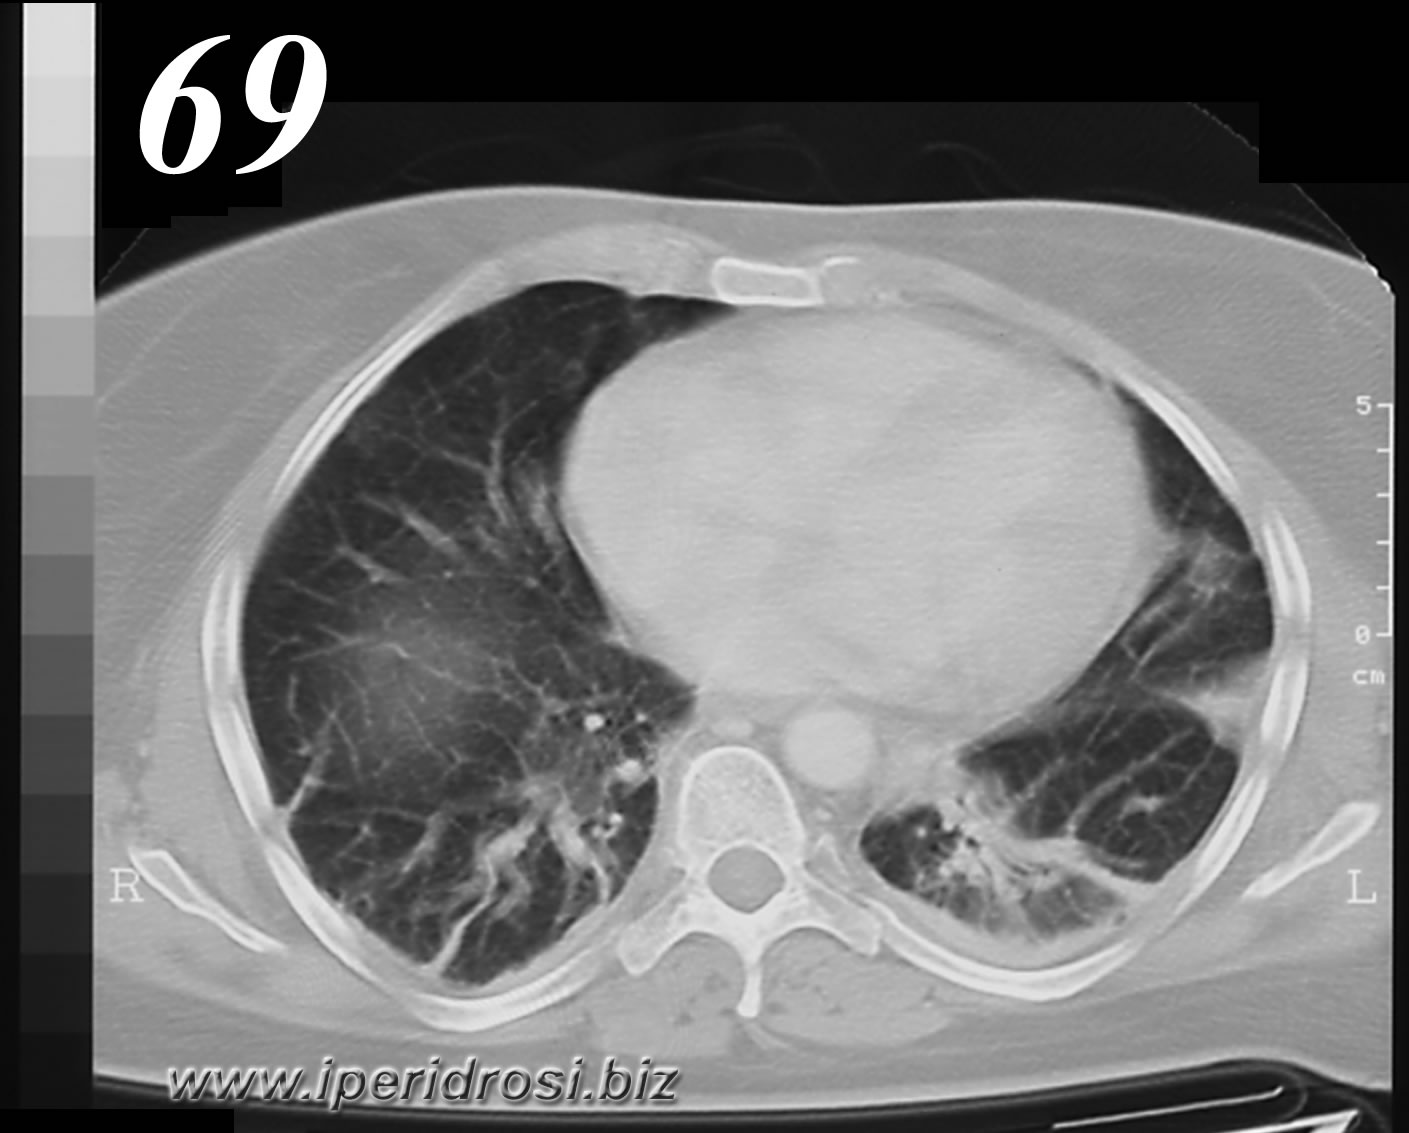

Al presente controllo appare discretamente ridotta la falda versamentale pleurica saccata in sede ascellare posteriore sinistra. Permangono strie distelettasiche ai piani basali ad ambedue i polmoni. Invariati i linfonodi mediastinici ed ascellari. Si osserva ulteriore notevole riduzione della raccolta liquida sottoepatica, di cui residua minima falda laminare. Non raccolte fluide pelviche.